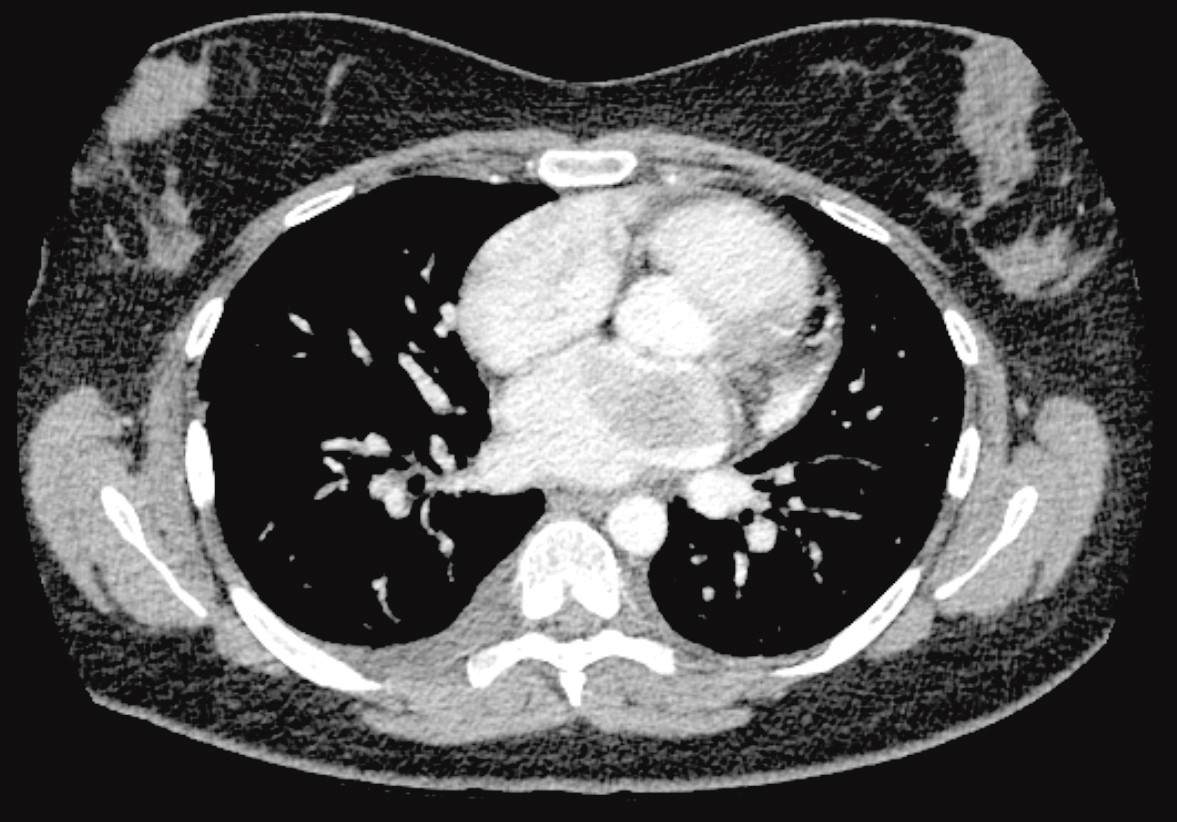

Bildediagnostisk utredning med røntgen thorax (figur 1) viste funn som kunne passe med stuvning. Pasienten var ung uten kjent hjertesykdom, og man vurderte derfor stuvning som mindre sannsynlig. Ut ifra røntgenbildene ble det reist mistanke om luftveisinfeksjon eller mulig interstitiell lungesykdom, differensialdiagnostisk stuvning. CT thorax (figur 2) avdekket en oppfylning i venstre atrium og bekreftet tegn til stuvning. Ekkokardiografi viste en stor ekkohomogen, velavgrenset og stilket tumor utgående fra atrieseptum, som nær utfylte venstre atrium og i diastole obstruerte mitralostiet. Funnet ga mistanke om myksom. Hun hadde sikker leiebetinget dyspné ved undersøkelsen.

Pasienten ble overflyttet til universitetssykehus og operert med eksisjon av tumor i venstre atrium nær septum. Peroperativt avdekket man ytterligere en tumor i venstre atrium ved bakre mitralannulus, som også ble eksidert. Få uker etter operasjonen ble det overraskende påvist residiv i venstre atrium. I tillegg var det separate tumorsuspekte lesjoner i høyre og venstre atrium. Den histologiske diagnosen viste seg å være intimalt sarkom. Positronemisjonstomografi (PET)-CT påviste to metastaser i magesekken.